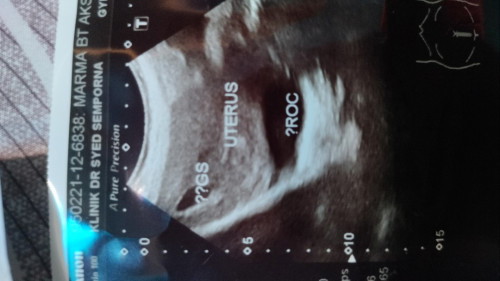

3 bln dh lwat haid kmrin ada bt upt ve+ dn sy g klnik Blum nmpk pape ada yg mcm ni ke Haid x trtur

Baca lagiI pun irregular period. Lama tak period so i tak check. Tiba2 rasa nak check sebab breast rasa sakit and sakit2 pinggang. Alhamdulillah that time dah 6weeks pregnant. Scan nampak kantung. Datang lagi masa 9weeks baru nampak baby and boleh dengar heartbeat. Hope ada rezeki awak sis. Doa banyak2 ye

Normal sis. Saya pun period 3 bulan sekali. So scan tak sama dengan LMP. Positive bulan 11,rupanya lekat baby time pertengahan bulan 10(ovulation) . So sis tenang tenang dulu, nanti 2-3 weeks, scan balik. Ada janin baru dapat tahu exact umur baby bila😁

kalau haid tak teratur normal je tu. doktor ada suruh repeat scan lepas 2 minggu tak?